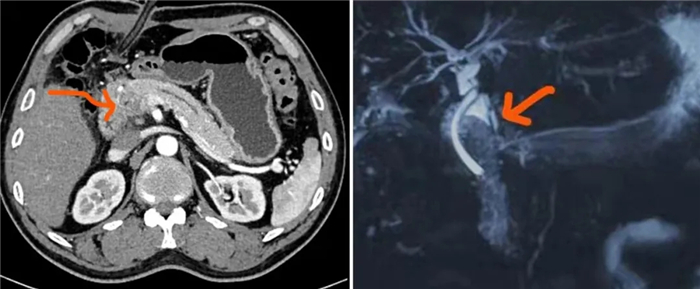

胰十二指肠切除术是外科手术中的一项高要求且复杂的手术,在胰十二指肠切除手术过程中,需将胰头、十二指肠和胆总管进行切除并重建,这样的手术对外科医生来说最具挑战性。而胰瘘一直都是术后最常见、最严重的并发症,其危害性主要在于被胆肠液激活的胰液漏入腹腔,腐蚀周围组织,非常容易引起致命性大出血或不易控制的感染,造成患者死亡。

为了降低并发症带来的严重后果,西藏大学附属阜康医院普外科通过不断探索,改良并创新了胰肠吻合术的术式,在防止胰瘘方面初步显现了其优势,使患者在很大程度上获益。

目前,该项术式已在手术中得到应用,术后患者均未发生胰瘘现象,并且在多次回访的过程中,患者的各项指标都在正常范围内。